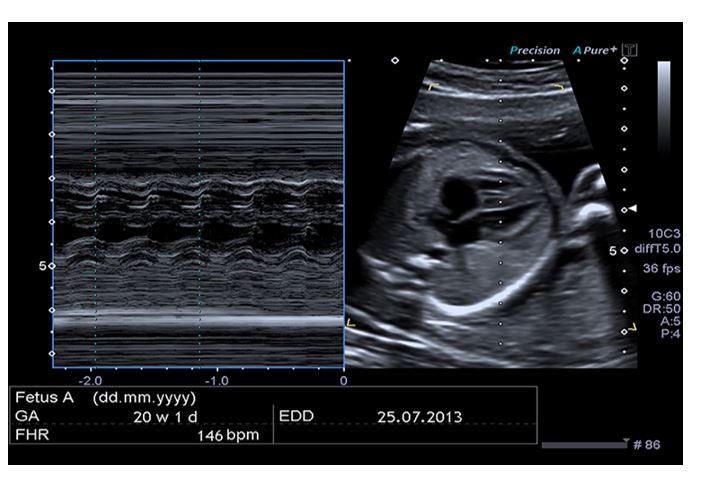

Tachycardia was identified in this patient with a heart rate of 246 beats/min.

___________ caused by cardiac insufficiency is one of the most common causes. Cardiac insufficiency can result from cardiac anomalies or arrhythmias .

Nonimmune hydrops